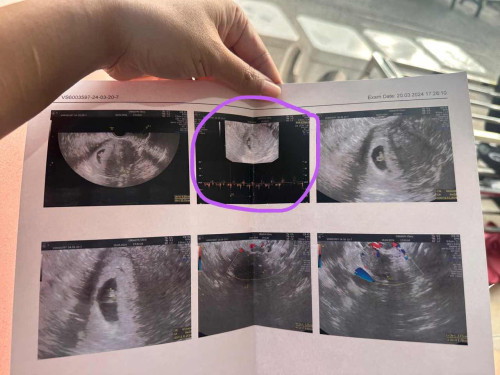

อายุครรภ์6สัปดาห์แม่แพ้ท้องมากไปหาหมอขอรับยาแก้แพ้หมอเลย ซาวด์ดูเจ้าตัวเล็กให้เลยภาพที่แม่วงกลมคือเสียงหัวใจดวงน้อยๆกำลังเต้นเพื่อนๆ6สัปดาห์เป็นยังไงกันบ้างแชร์กันได้นะคะ#ขอบคุณล่วงหน้าสำหรับความคิดเห็นค่ะ ❤️❤️❤️❤️❤️❤️❤️